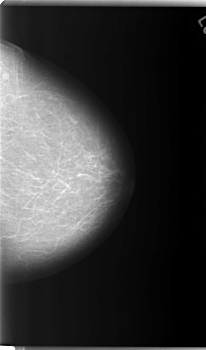

C_0086_1.LEFT_MLO

LEFT_CC LINES 5936 PIXELS_PER_LINE 3496 BITS_PER_PIXEL 12 RESOLUTION 50 NON_OVERLAY

LEFT_MLO LINES 5896 PIXELS_PER_LINE 3576 BITS_PER_PIXEL 12 RESOLUTION 50 NON_OVERLAY